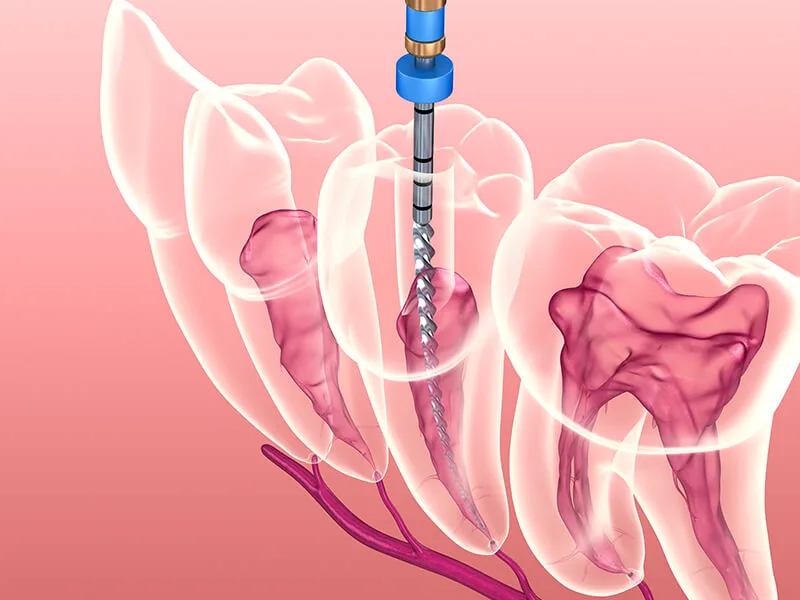

Esta área da odontologia foca especificamente no cuidado da polpa dentária, o tecido interno do dente que contém nervos e vasos sanguíneos.

O uso de tecnologia avançada em um consultório especializado em endodontia é um diferencial que transforma a experiência do paciente, tornando procedimentos complexos muito mais simples e seguros.

Tecnologia: Uso de microscopia operatória e localizadores apicais para exatidão milimétrica;

Equipamentos Modernos: Sistemas rotatórios e radiografia digital que agilizam o diagnóstico e a execução;

A utilização de recursos de última geração aumenta a eficácia dos procedimentos, permitindo que tratamentos de canal sejam finalizados com rapidez e precisão.

Preparação e Exames: Realização de imagens digitais para mapear a situação da polpa dentária;